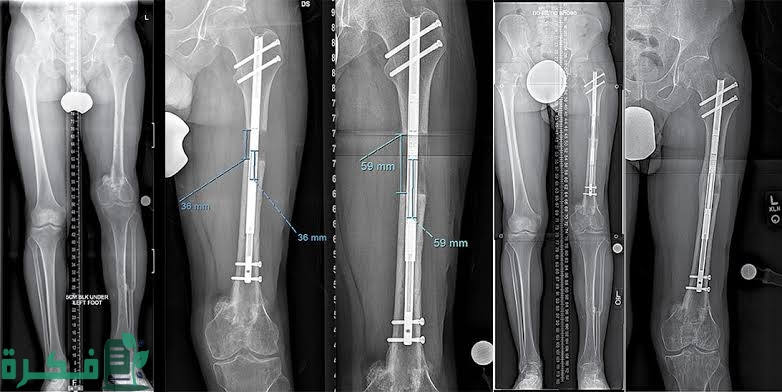

- ان المسمار النخاعي هو عباره عن وسيله طبيه لتثبيت العظام المكسوره.

- المسمار النخاعي هو عباره عن مسمار طويل يتم وضعه في قناة نخاع العظام وذلك للعظام الطويلة مثل عظم الفخذ وعظم الساق.

- كما ان تركيب المسمار النخاعي يتم تركيبه في بعض أنواع الكسور ومنها الفخذ أو عظام الساق أو أحد العظام الطويلة.

- ويكون لكل مسمار نخاعي سمك وطول يختلف عن غيره من المسامير ويختار الطبيب طول وسمك المسمار المناسب.